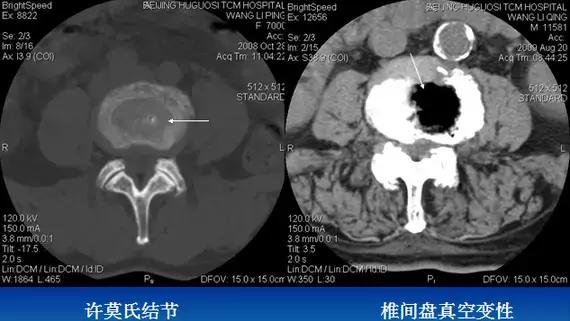

2、椎间盘真空变性:椎间盘见气体密度影,形成真空征。

3、许莫氏结节(schmorl’s nods):又称髓核压迹。